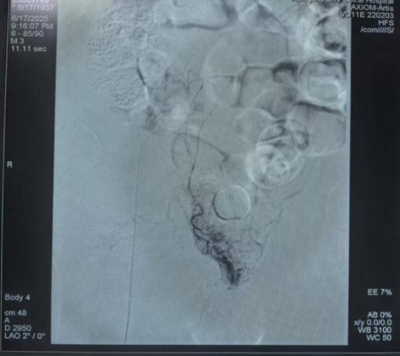

术前前列腺动脉明显增粗,紊乱